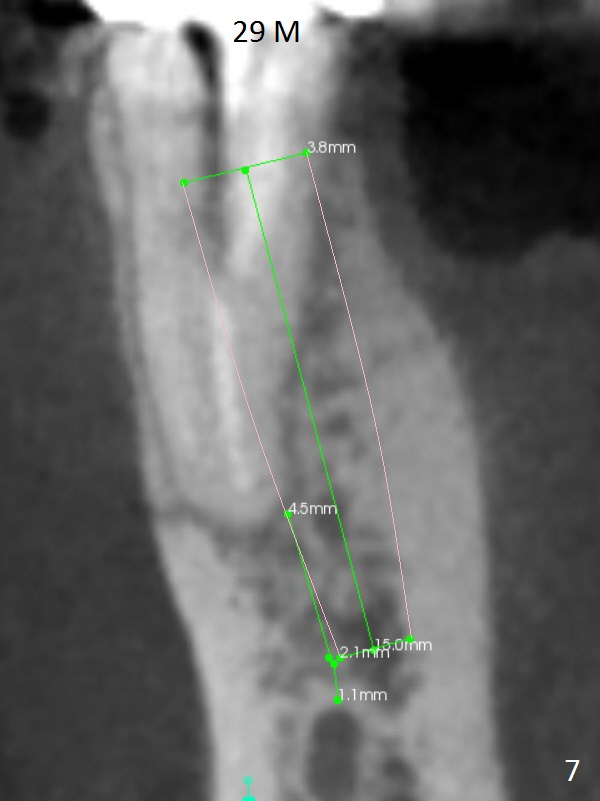

A 50-year-old man has pain and swelling buccal to the tooth #29 with large distal radiolucency (Fig.1 *). The bridge will be sectioned between #30 and 31. The mesial segment of the bridge is expected to separate from #29 post space; the mesial abutment is presumed to have vertical fracture (Fig.4 red line or root perforation due to oversized post (>)). After intraligamental injection, extraction and no Antibiotic treatment, a narrow long implant (Fig.6,7: 3.8x15 or 13 mm) will be placed as mesial and lingual as possible to avoid the buccal bony defect (Fig.5 >; repaired with Osteotape or PRF membrane) and the Mental Loop (Fig.1 >).